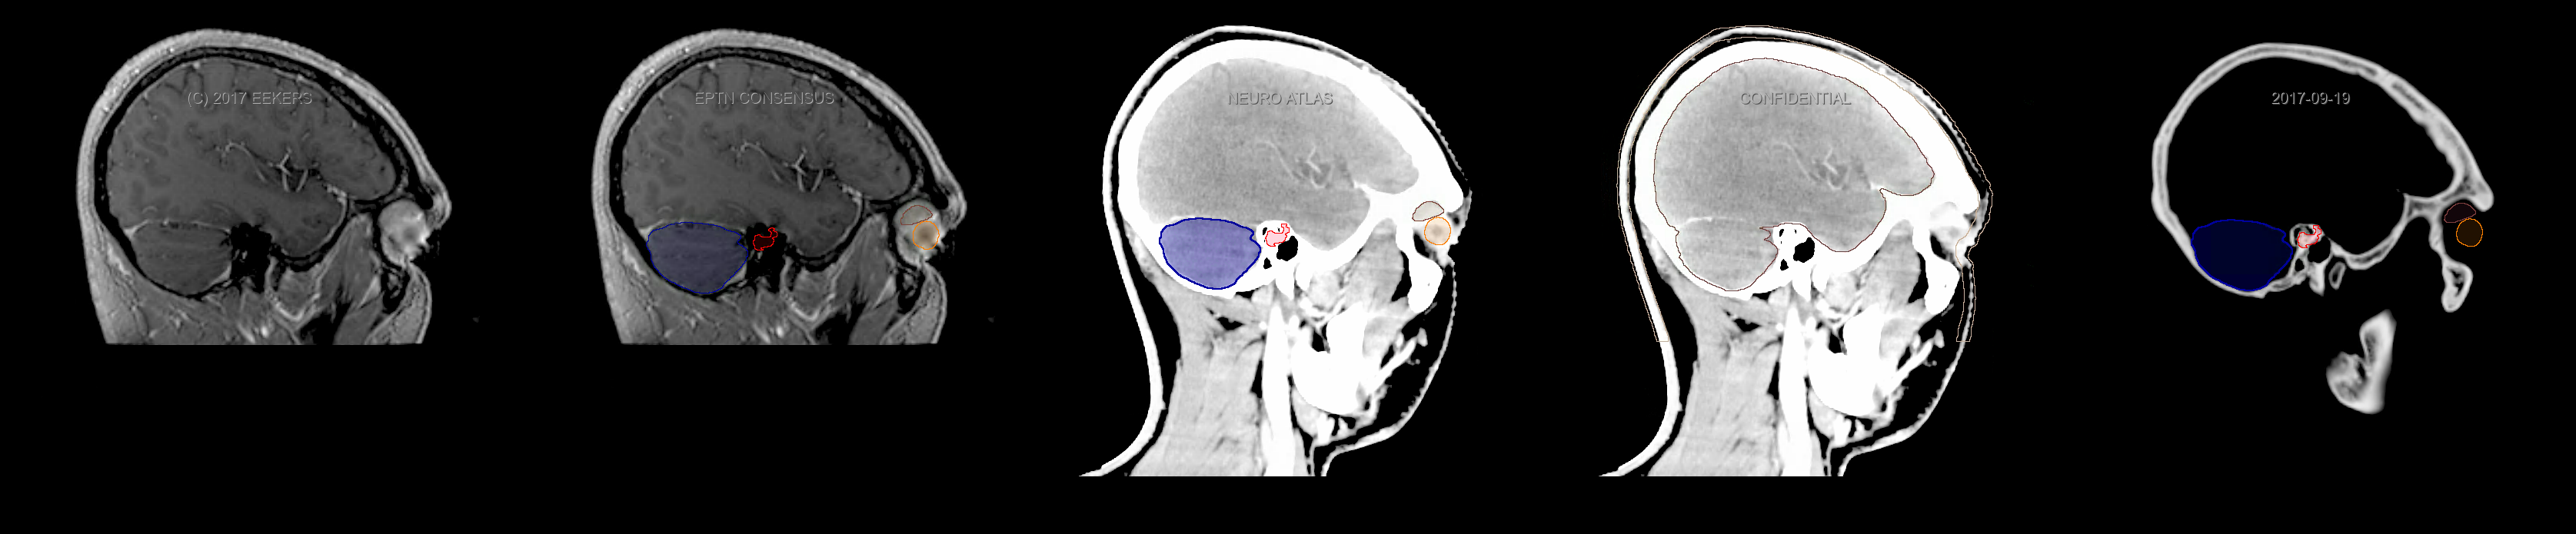

Eekers et al. have published an international neurological atlas for contouring of organs at risk in consensus with the European Particle Therapy Network (EPTN). The purpose of this consensus atlas is to decrease inter- and intra-observer variability in delineating OARs relevant for neuro-oncology. We propose this atlas is used in photon and particle therapy in order to derive consistent dosimetric data. When required this atlas will be updated according to new insights.

Included are all OARs known to be relevant for radiation-induced toxicity in neuro-oncology: brain, brainstem, cochlea, vestibulum & semicircular canals, cornea, lens, retina, lacrimal gland, optic nerve, chiasm, pituitary, hippocampus and skin. A new OAR relevant for neuro-cognition, the posterior cerebellum is also included.

Three-dimensional delineation of the fifteen consensus OARs for neuro-oncology are shown on CT and 3 Tesla (3T) MR images (slice thickness 1 mm with intravenous contrast agent). All are presented in transversal, sagittal and coronal view.

From left to right: MR without structures, MR with structures, CT (WW/WL 120/40) with structures, CT (WW/WL 120/40) with Brain and Brainstem Surface, CT (WW/WL 1500/120)with structures